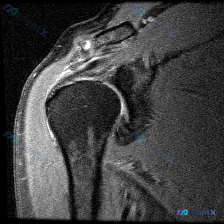

最近整理了一份肩部MRI的病例讨论材料,患者主要问题是肩部疼痛,但问题明确指向"盂唇病变"范畴。先看T2冠状位图像的关键发现: 1. 冈上肌腱在肱骨大结节止点处有显著高信号,连续性可能中断 2. 肩峰下-三角肌下滑囊有明显的高信号积液 3. 关节盂唇区域信号存在改变 大家觉得这个病例更符合哪种诊断?...

最近看到这份肩部MRI病例,问题问的是影像里的软组织积液怎么解释,整理了完整的读片和分析思路分享给大家。 一、影像基本信息 这是一张肩关节冠状位T2序列MRI,扫描范围覆盖肩峰、肩锁关节、冈上肌肌腱、肱骨头、肩关节间隙和三角肌,我们先明确正常信号基准:T2序列正常肌腱是低信号(黑色),关节液、水肿是...

看到一个肩关节MRI影像分析的病例材料,影像为冠状位T2加权图像,主要发现如下: 1. 冈上肌腱远端附着处全层撕裂,T2序列显示高信号液体填充 2. 肩峰下-三角肌下滑囊内有明显积液 3. 盂肱关节腔内有显著液体潴留 用户的核心问题是关于「盂唇病变」的可能性。这个病例有几个点值得讨论: - 冈上肌腱...